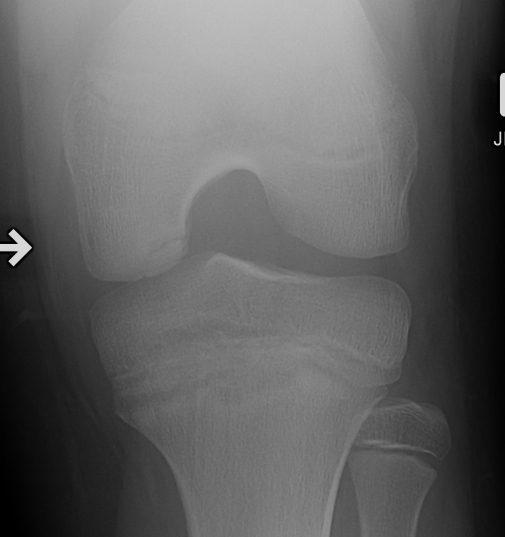

Xray

Intercondylar view / notch / tunnel view imperative

- most commonly seen in this view

- can miss the lesion unless have flexed knee view 30-50o

Xray classification

Stage 1: Normal / abnormal MRI

Stage 2: Lucent area of subchondral bone, can have surrounding sclerosis

Stage 3: Partial loosening

Stage 4: Completely detached / loose body

Type 2 Type 3 Type 3